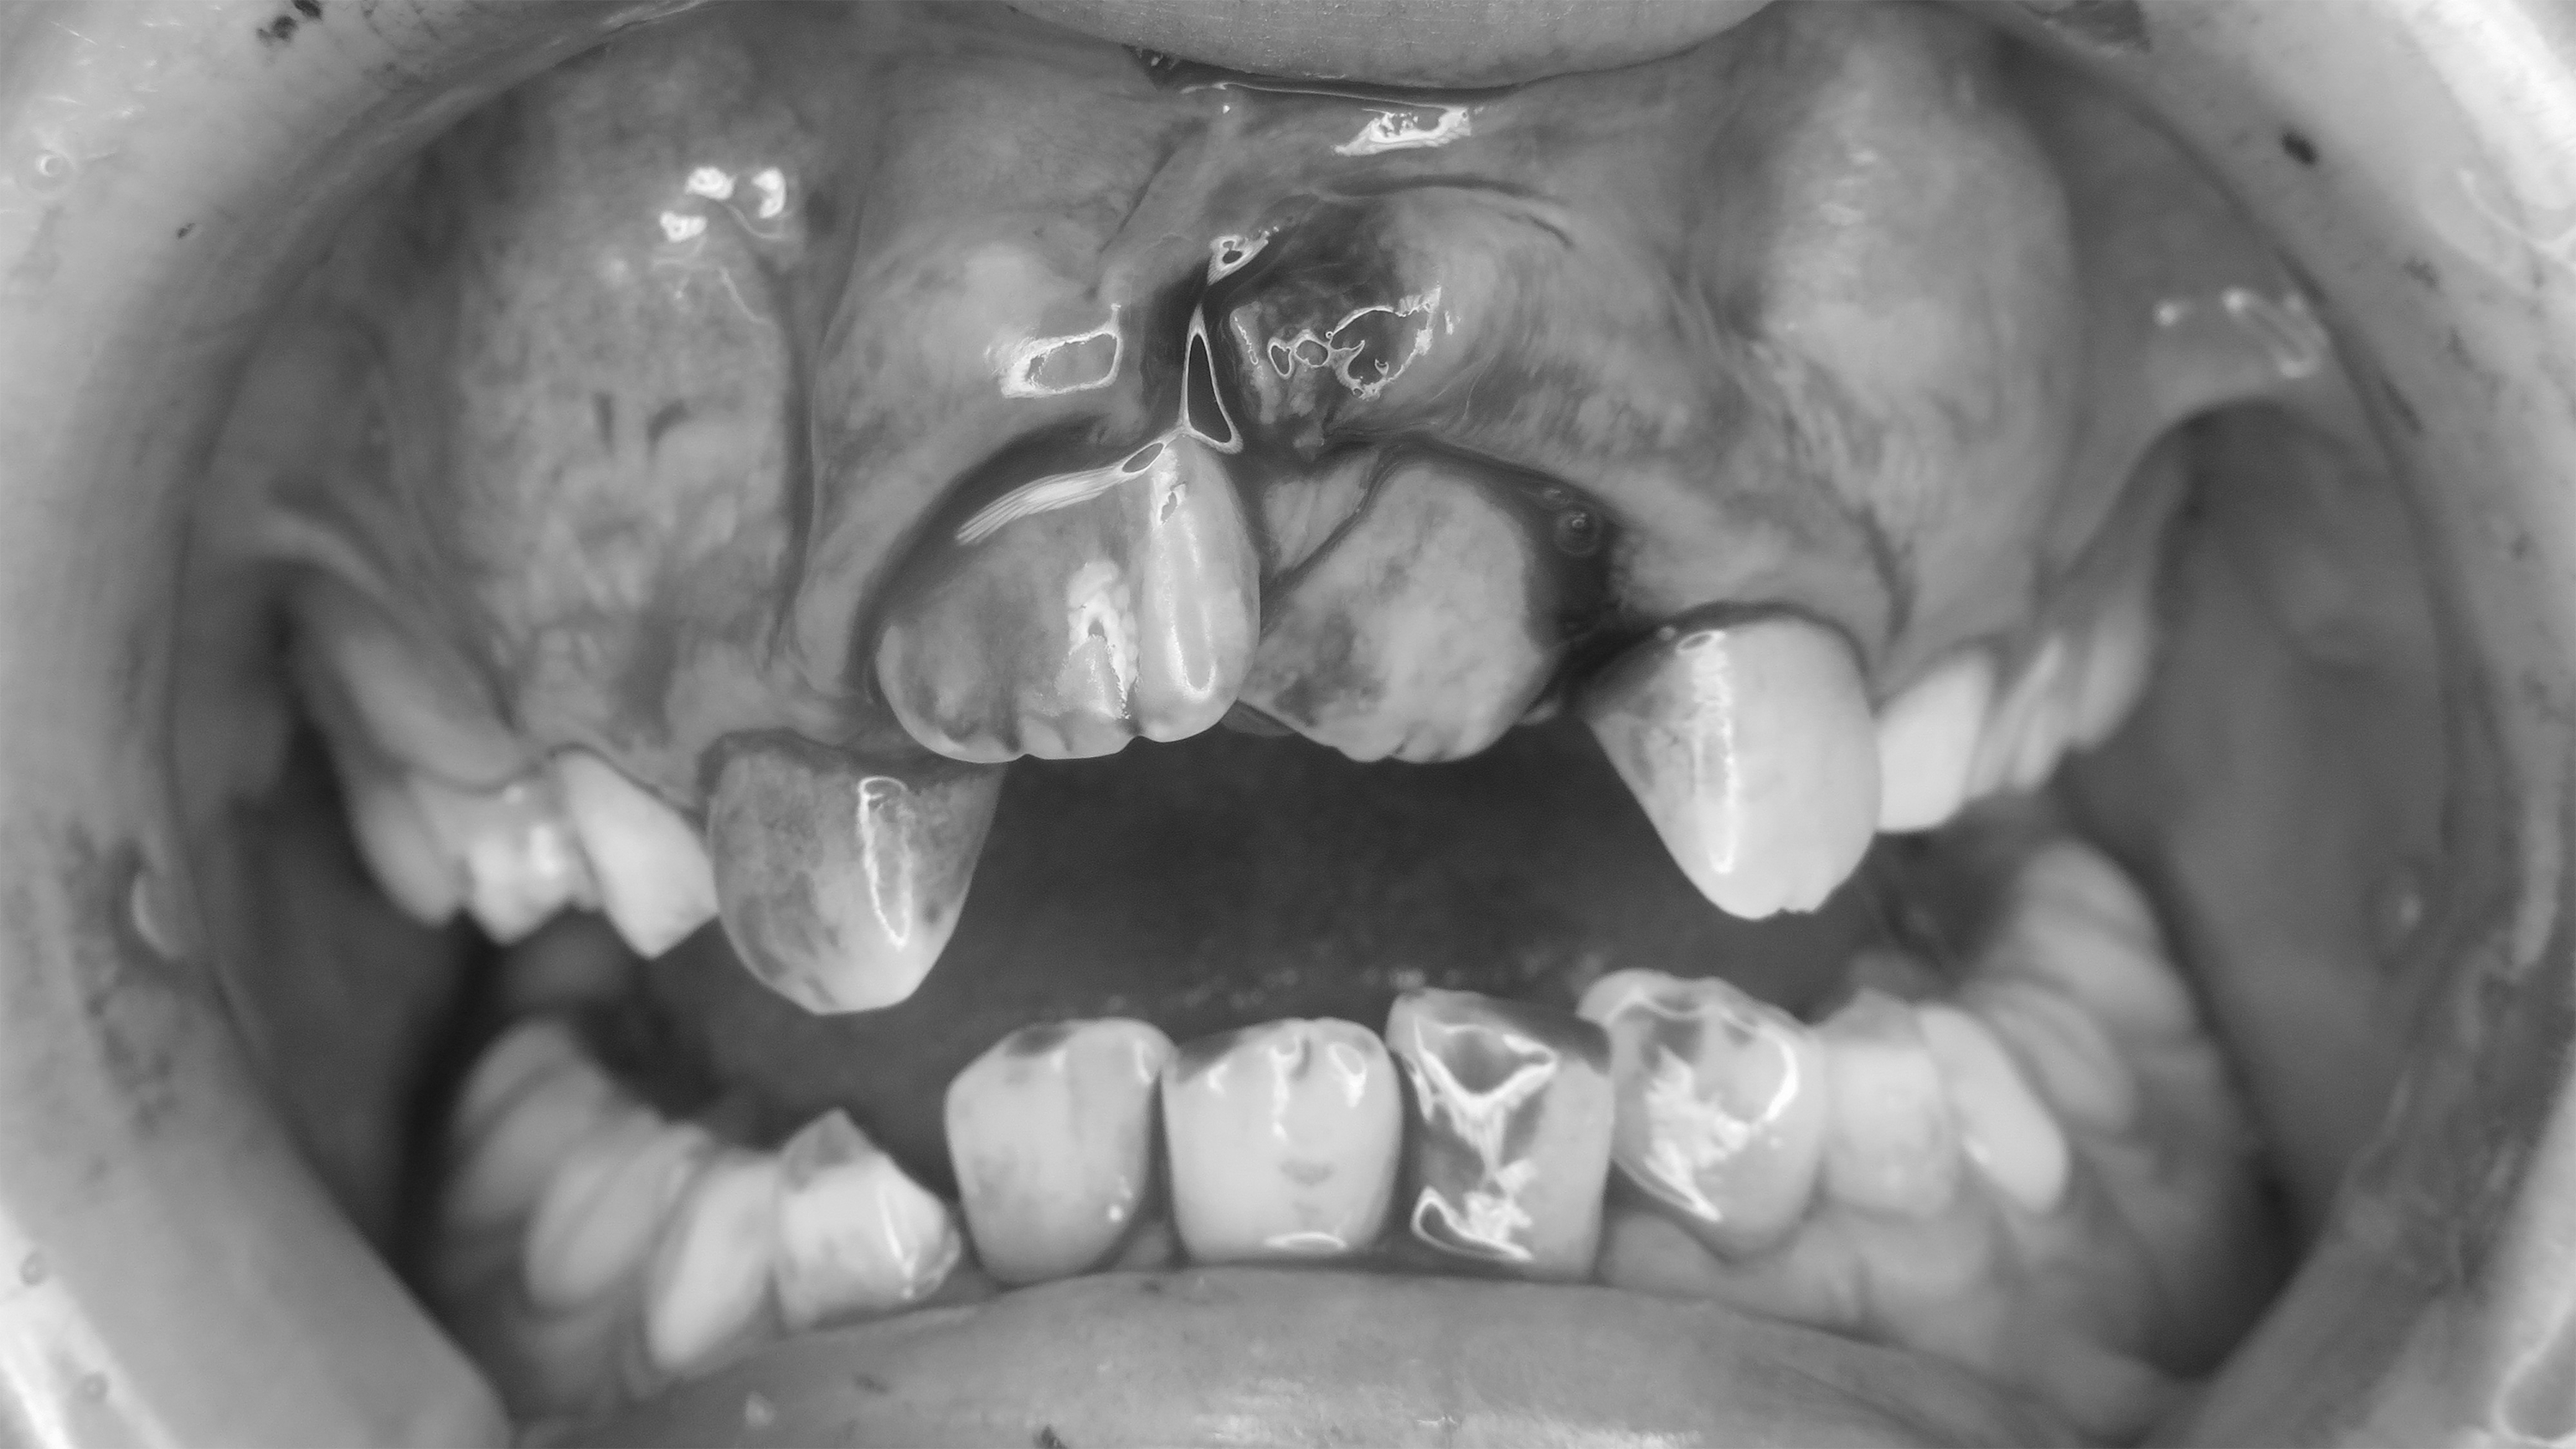

Dislokationsverletzungen im bleibenden Gebiss treten im klinischen Alltag meist plötzlich und unerwartet auf und erfordern eine rasche und strukturierte Befundung sowie eine notfallmässige Erstversorgung. Besonders bei Dislokationsverletzungen wie Avulsion, lateraler Dislokation, Extrusion und Instrusion ist die Initialversorgung ein entscheidender prognostischer Faktor für den Zahnerhalt. Am Zahntraumasymposium 2026 stehen genau diese Verletzungsmuster im Fokus. Anhand aktueller Leitlinien, Fallbeispiele und praxisnaher Empfehlungen soll vermittelt werden, wie eine strukturierte Erstbeurteilung und Notfallbehandlung im bleibenden Gebiss idealerweise erfolgt – Kompetenzen, die jede Zahnärztin und jeder Zahnarzt im klinischen Alltag sicher beherrschen sollte.